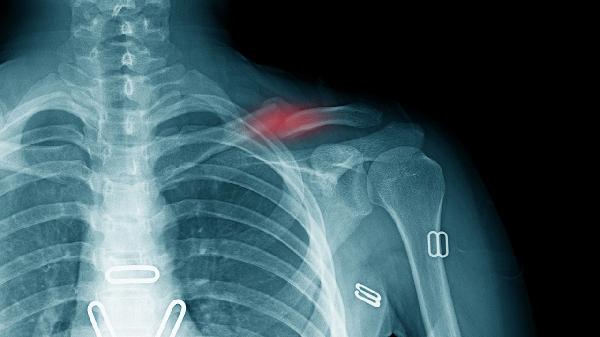

骨折端对位不良是保守治疗失败的常见原因。需由骨科医师在影像引导下进行闭合复位,纠正成角或重叠移位。复位后需定期复查X线片确认位置维持,儿童患者建议每周复查,成人可间隔2周。若反复复位超过3次仍无法维持对位,需考虑其他干预方式。

当出现骨折端分离超过2厘米、皮肤即将穿透、血管神经损伤等绝对手术指征时,需行切开复位内固定术。常用术式包括解剖型锁骨钢板固定或弹性髓内钉固定。术后早期开始被动关节活动,6周后逐步过渡到抗阻力训练,通常3个月可恢复日常活动。